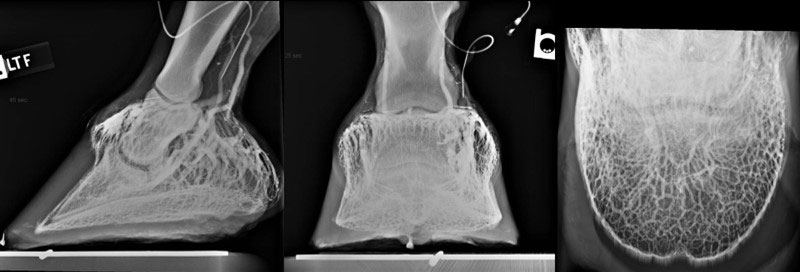

The lateral, dorsopalmar and solar radiographic views of the venogram show the areas of the foot where the circulation can be assessed.

IMAGE COURTESY OF MARK SILVERMAN, DVM